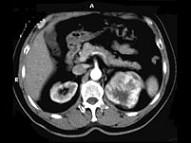

问题 男,65岁,左侧腰背部胀痛伴无痛性全程血尿3个月余,CT平扫及增强检查如图所示,下列说法正确的是 ( )

选项 A、考虑为左侧肾癌 B、考虑为左侧肾错构瘤 C、增强扫描肾皮质期可见肿块明显强化,其内亦有无强化区 D、增强扫描肾实质期可见肿块强化迅速下降,但密度比平扫时仍要高 E、平扫时见左肾上极有一软组织肿块影,其边界较清楚

答案 ACDE